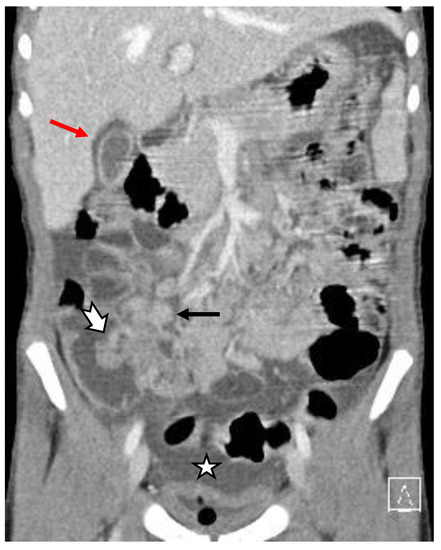

- Abnormalities of the hollow visceral organs, including distension and wall thickening of the gallbladder (Figure 4), stomach, bowel, small bowel (Figure 5A, and urinary bladder (on CT and ultrasound). They were considered thickened if >3 mm. Additionally, the cross-sectional diameter of appendix is considered enlarged if >6 mm (Figure 5B).

- Peritoneal abnormalities—ascites (Figure 6), fluid collections, and pneumoperitoneum.

- Mesenteric and retroperitoneal lymphadenopathy (Figure 7) with mesenteric lymph nodes considered enlarged if >5 mm in short axis and retroperitoneal lymph nodes considered enlarged if >9 mm in short axis.